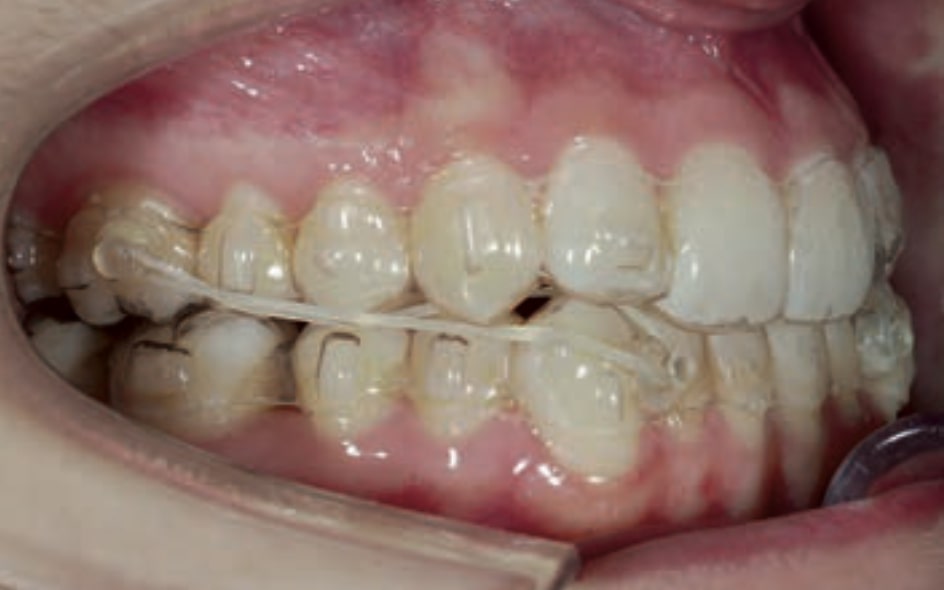

- Distalization of the Third and Fourth Quadrants: Move the teeth distally in these quadrants to achieve a Class I relationship using the A8 protocol, improving the patient’s dental alignment and occlusion.

- Solve the Crossbite of Tooth 33: Correct the position of tooth 33 to eliminate the crossbite, contributing to a more balanced occlusion.

Treatment setup

Treatment progress